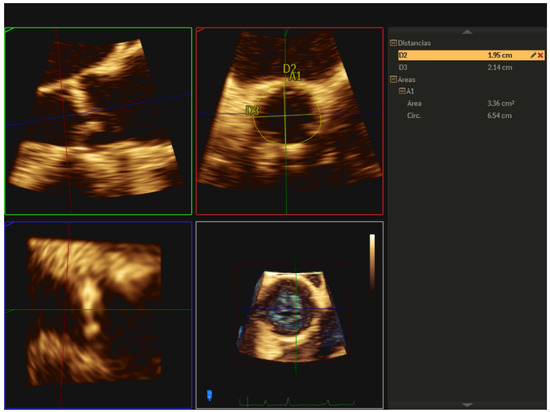

| 1 | Three-dimensional TEE allows us to accurately evaluate the aortic valve morphology and measure the valve annulus prior to TAVR implantation, helping us to choose the appropriate size of the prosthesis, especially useful in cases where the cardio-CT is not of adequate quality. |